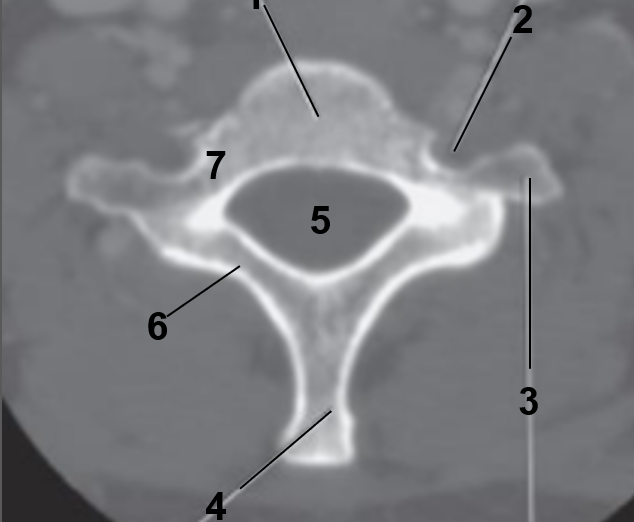

1

Body of thoracic vertebrae

2

Vertebral foramen

3

transverse process